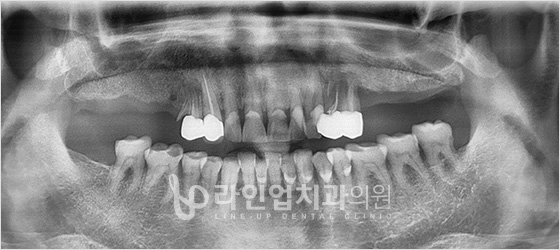

Before

After

Upper molars implant